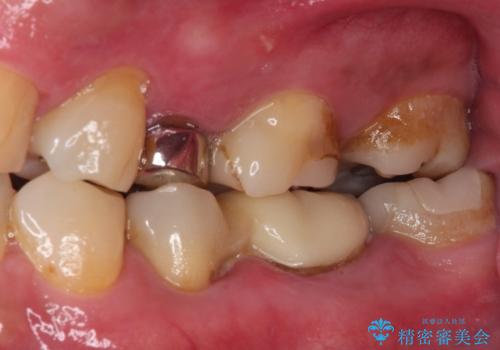

詰め物の外れてしまった奥歯 部分矯正で歯列を整えてから補綴治療